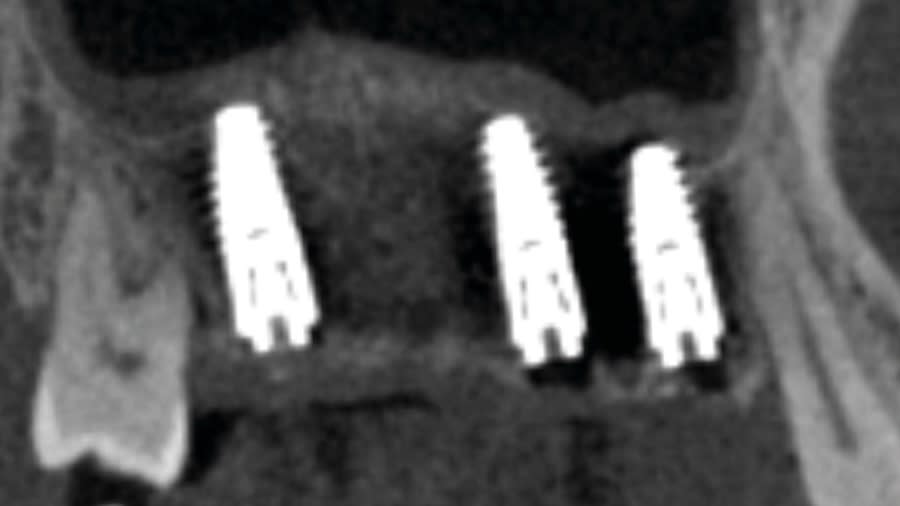

Step 4: Allow 4 to 6 months for the sinus graft healing. CBCT evaluation is needed to evaluate the available regenerated bone height for the implant placement. Reflect soft tissue utilizing standard surgical instruments, and use Densah burs for osseodensification site preparation to prepare the implant osteotomy and place the implant.

Case 1 (Figure 3 through Figure 24) depicts a 3-year follow-up of combined osseodensification sinus protocol IV in a severely resorbed maxillary ridge with ≤0.5 mm bone height in molar sites and horizontal deficiency at the first premolar site, using a two-stage approach for implant placement.

The presented protocol describes a crestal sinus elevation procedure using osseodensification burswith vertical stops (Versah) in severe cases with <2 mm of residual bone as a predictable technique, with successful bone regeneration for second-stage implant placement with subsequent stable peri-implant bone level at 3-year follow-up. This technique, thus, offers a simplified, minimally invasive, and less traumatic method for sinus floor elevation in cases with severe residual bone height loss.